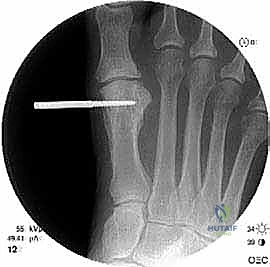

الخطوة الثالثة: قص العظم (Osteotomy)

باستخدام منشار جراحي ميكروسكوبي دقيق، يقوم الدكتور هطيف بقص عظم مشط القدم. تعتمد زاوية وشكل القص (مثل القص المائل أو القص على شكل حرف Z) على مقدار الإطالة المطلوبة وشكل العظم المتبقي من الجراحة السابقة.

الخطوة الخامسة: التثبيت الداخلي القوي (Internal Fixation)

لضمان التئام العظم في وضعه الجديد والطويل، يجب تثبيته بقوة شديدة. يستخدم الدكتور هطيف أحدث الشرائح المعدنية التيتانيوم ذات الزاوية الثابتة (Locking Plates) والمسامير الدقيقة. هذا التثبيت القوي يمنع أي حركة بين العظام ويسمح ببدء العلاج الطبيعي في وقت مبكر.